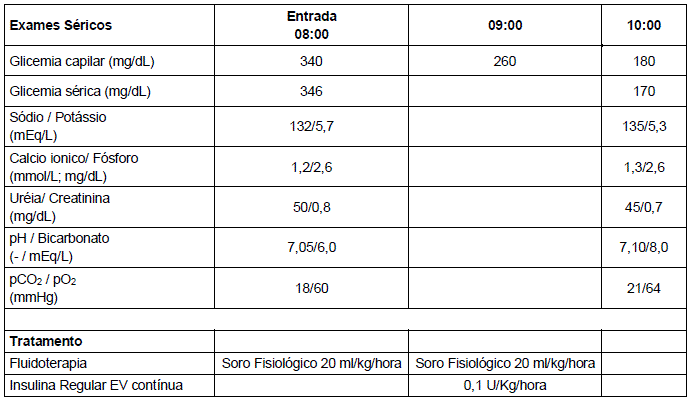

Menina, 6 anos de idade, com antecedente de Diabetes Mellitus tipo 1, em uso regular de insulina NPH, foi admitida no serviço de emergência há 2 horas, devido a quadro de vômitos e dor abdominal há 3 dias. Os exames coletados e as medidas realizadas na sala de emergência estão descritos na tabela abaixo.

Ao exame, paciente encontra-se em regular estado geral, mucosas secas, FC: 115bpm, frequência respiratória de 35 ipm, PA 90/50 mmHg, tempo de enchimento capilar de 4 segundos. Queixa-se apenas de fraqueza. Dentre as medidas a serem realizadas na terceira hora, inclui-se: